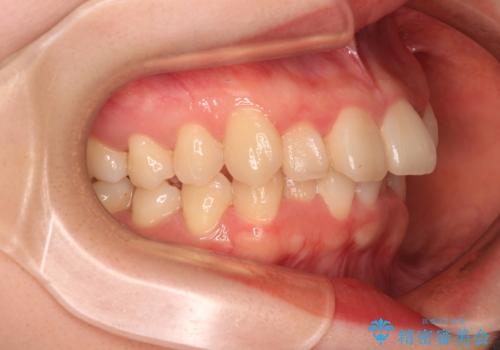

マウスピースでもワイヤー装置でも対応可能でしたが、右側の咬み合わせが上顎がやや前方に位置していることから、補助装置を使用することが推奨されました。

右上と左下の第一大臼歯2本が周辺の歯と比べて位置がずれていたため、ゴムかけやワイヤーに曲げを入れることで移動を試みましたが、どうよら癒着をしており、移動困難と判断されました。

見た目や咬み合わせに違和感がないとのことで、癒着歯の無理な移動は試みずに治療を終えることとしました。